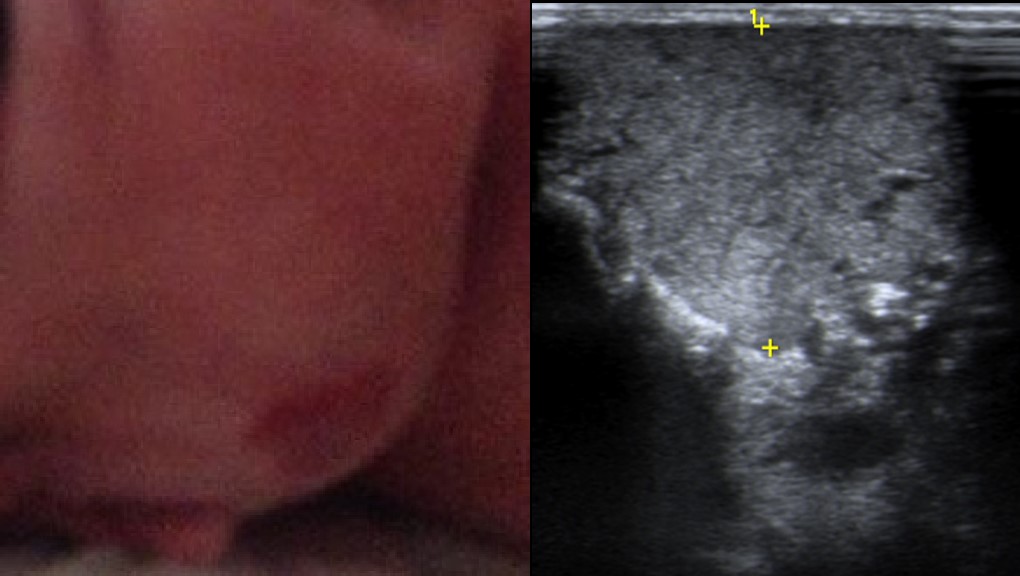

Na observação, documentou-se alteração da coloração cutânea vermelho vivo, protuberante e compressível (Fig. 1), sem outras alterações no exame objetivo. A avaliação laboratorial sumária não mostrou alterações.

A ecografia de partes moles demonstrou a presença de massa heterogénea, bem delimitada, com contornos lobulados, correspondendo à glândula parótida com alteração da sua ecoestrutura e volume (Fig. 1), sem extensão ou invasão dos planos adjacentes passíveis de avaliação, intensamente vascularizada (Fig. 2), com vasos de grande calibre no seu interior quer arteriais quer venosos.

Figura 1: À esquerda, tumefação pré-auricular direita, com alteração cutânea vermelho vivo. À direita, imagem correspondente de ecografia mostrando massa heterogénea, bem delimitada, com contornos lobulados, na topografia de glândula parótida.